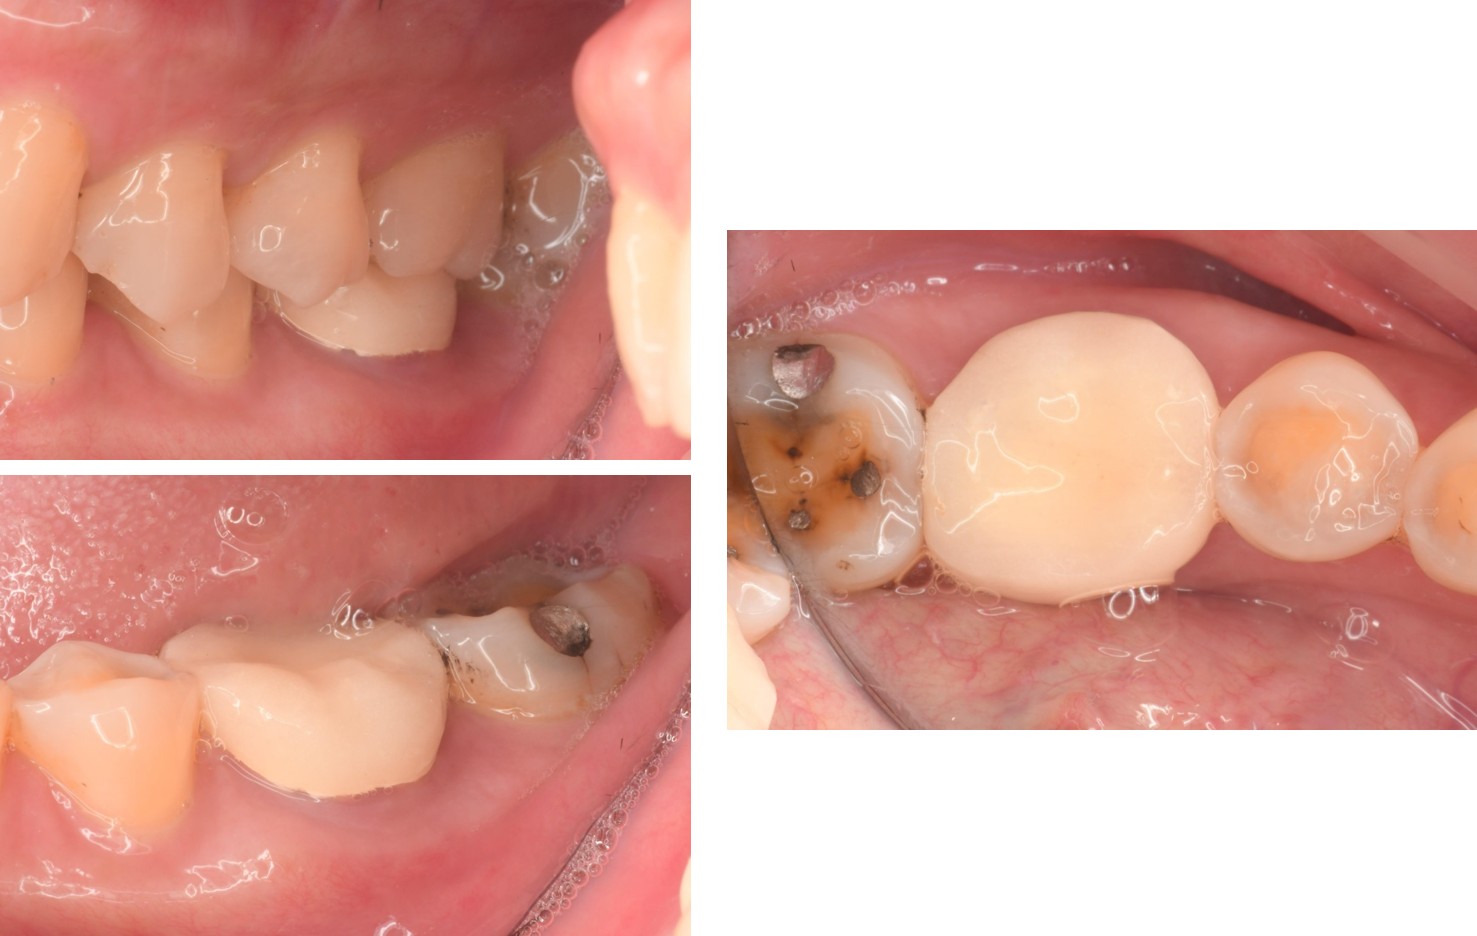

治療前,牙齦腫脹

治療前,根管治療不完全